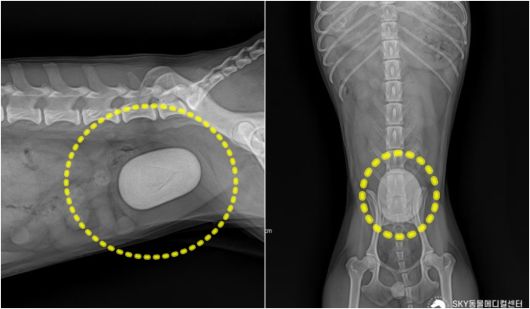

혈뇨 증상으로 동물병원에 내원한 푸들의 방사선 검사에서 발견된 거대 결석(광주 스카이동물메디컬센터 제공) ⓒ 뉴스1 |

스카이동물메디컬센터(SKY동물메디컬센터)에 따르면, 이 반려견은 최근 들어 소변에 피가 섞여 나오는 혈뇨 증상이 반복돼 병원을 찾았다. 방사선 검사 결과 방광 내부에 단일 결석으로 추정되는 대형 방광결석이 명확히 관찰됐다. 결석 크기가 상당해 방광 윤곽의 변형과 팽창이 동반됐다. 결석에 의한 방광 점막 자극과 염증이 의심되는 소견을 보였다.

초음파 검사에서도 방광 점막 전반에 걸쳐 불규칙한 에코 패턴이 확인됐다. 이는 결석이 장기간 방광을 자극하며 만성 방광염이 함께 진행된 상태를 시사하는 소견이다.